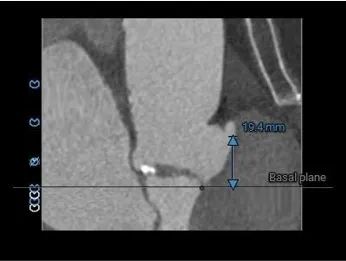

左冠15.7,右冠19.4,综合分析冠脉阻挡风险适中

• 左、右冠高度可,切线位测量,无冗长瓣叶,结合瓦氏窦、STJ 内径综合预估,冠脉阻塞风险适中